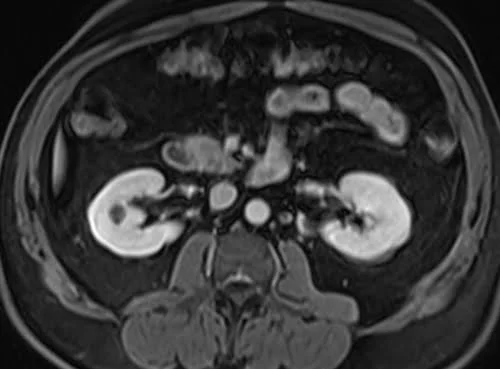

VIBE FAT SAT AXIAL POST CONTRAST SEQUENCE USED IN RENAL IMAGING

Kidneys :- bright

- Very useful for kidney imaging

- Very useful for kidneys imaging

The easiest way to identify T1 VIBE fat-saturated post-gadolinium images is to look for adipose tissues (e.g., subcutaneous fat and fat in bone marrow) and blood vessels in the body (e.g., arteries and veins in the chest, abdomen, upper limbs, and lower limbs). Areas containing adipose tissues appear dark on T1 VIBE fat-saturated post-gadolinium images. Blood vessels and pathologies with high vascularity appear bright on T1 VIBE fat-saturated post-gadolinium images. All other characteristics of the T1 VIBE fat-saturated post-gadolinium images remain the same as the T1 VIBE images.